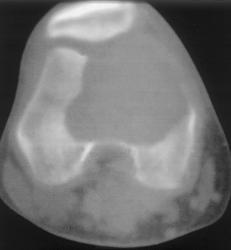

Гигантоклеточная опухоль.

Злокачественная гигантоклеточная  опухоль возникает из доброкачественной (частота 10-20%). После операции возможно появление рецидива опухоли.